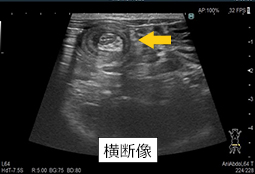

軟部外科は骨や神経以外の柔らかい組織を扱う外科です。避妊去勢手術から体表腫瘍の切除、腹腔内、胸腔内の腫瘍切除まで多くの範囲を含みます。